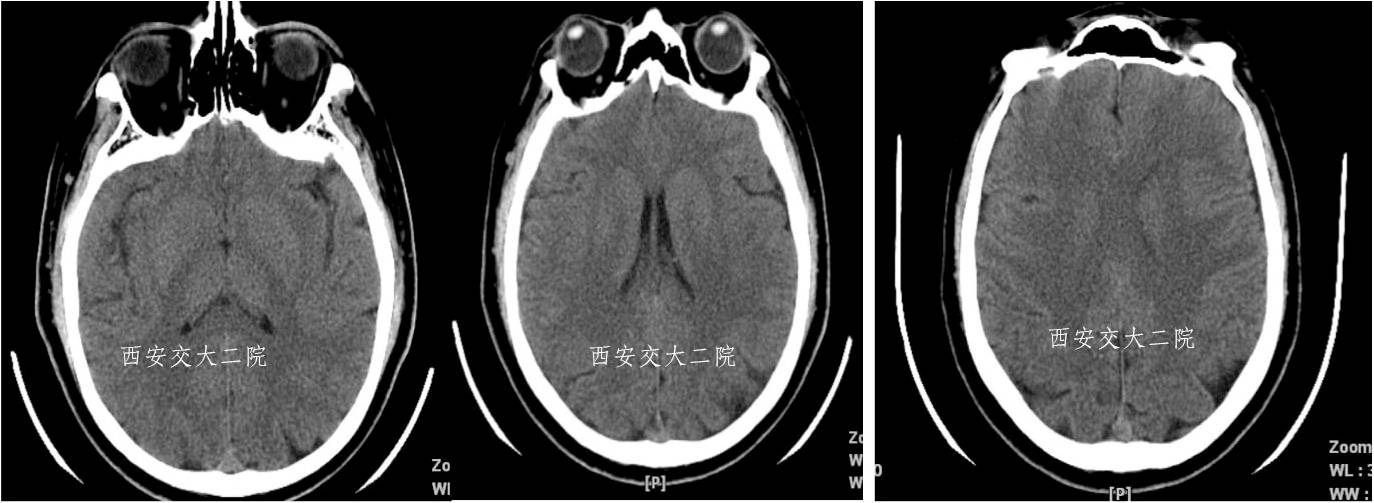

术前CT(病后1h)

术前DWI

病后2小时动脉推注阿替普酶5mg,无果;solitaire AB(4*20)取栓,闭塞的MCA再通。

术后即刻病情及脑CT

术后24小时脑CT